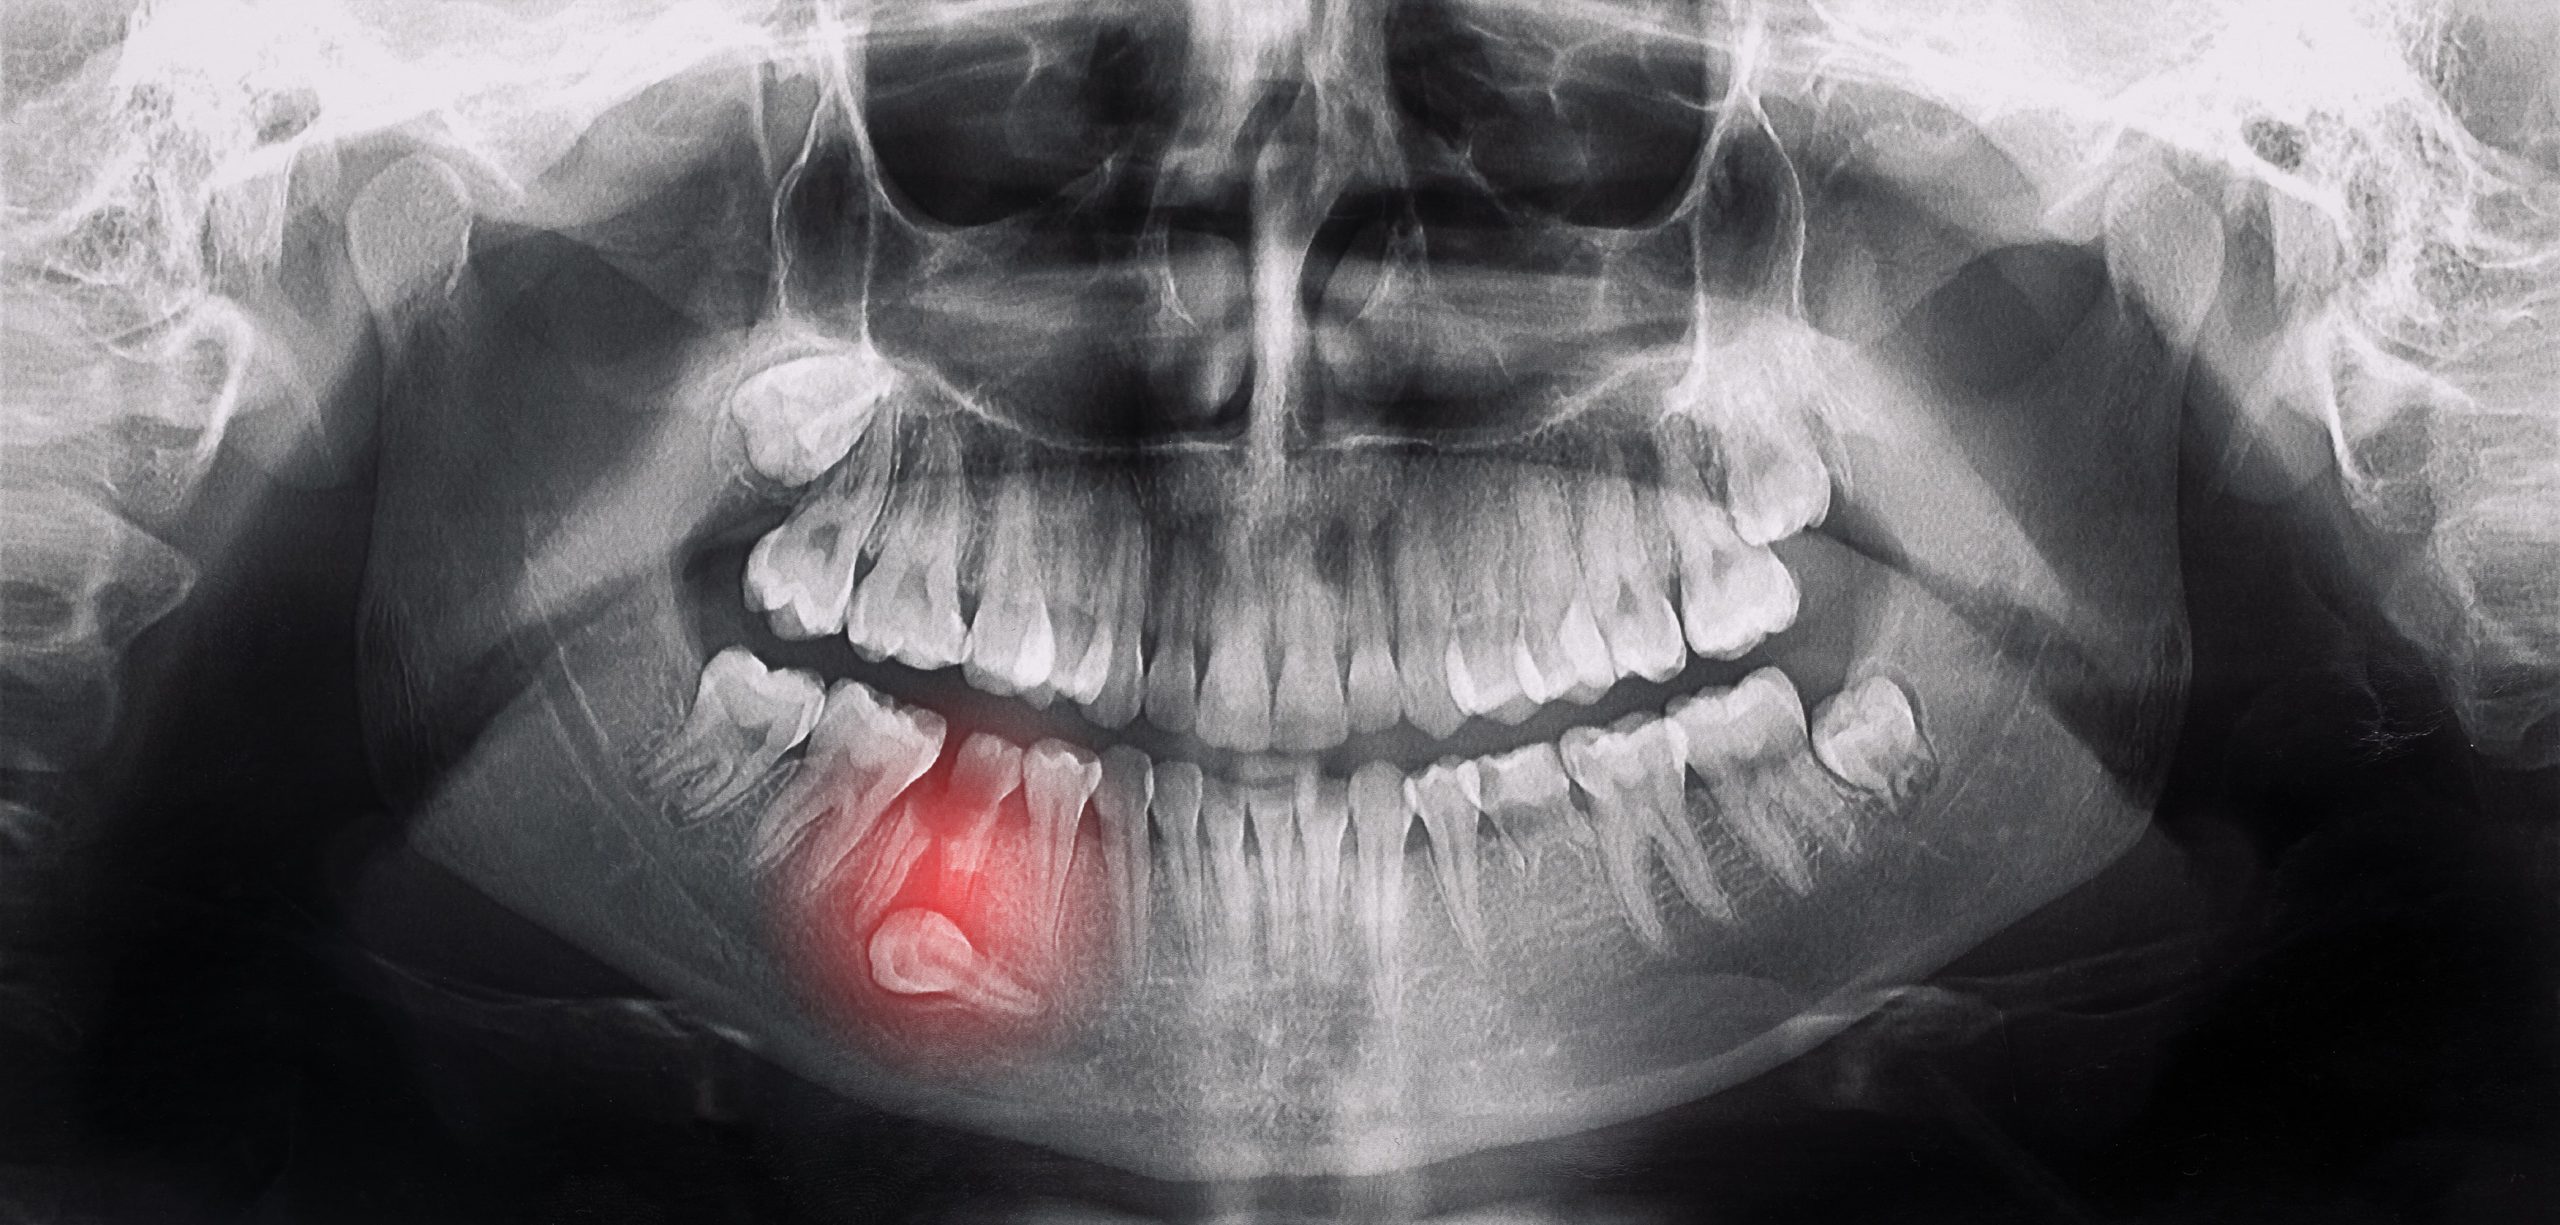

親知らずの抜歯について

親知らずは、最も奥に生える第三大臼歯のことで、多くの場合、10代後半から20代前半にかけて生えてきます。スペースが足りずに横向きに生えたり、一部だけ顔を出したりすることが多く、様々なトラブルを引き起こします。

当院では年間100本、30年間で3,000本以上の親知らず抜歯実績があります。横向き(水平)埋伏歯であっても、十分な麻酔を効かせてから10分ほどの処置時間で抜歯いたします。術後の腫れをできるだけ抑えるため、テルプラグを使用しております。

患者様のご要望があれば一度に複数本抜くこともありますが、静脈内鎮静麻酔は使用せず、局所麻酔で対応いたします。短時間に要領よく抜くことで、術後の腫れや痛みを最小限に抑えることができます。

- 02検査と治療計画のご説明

- 口腔内を詳しく診察し、必要に応じてレントゲン撮影やCT撮影を行います。画像診断により、歯や骨の状態を正確に把握します。診断結果に基づき、最適な治療法をご提案いたします。